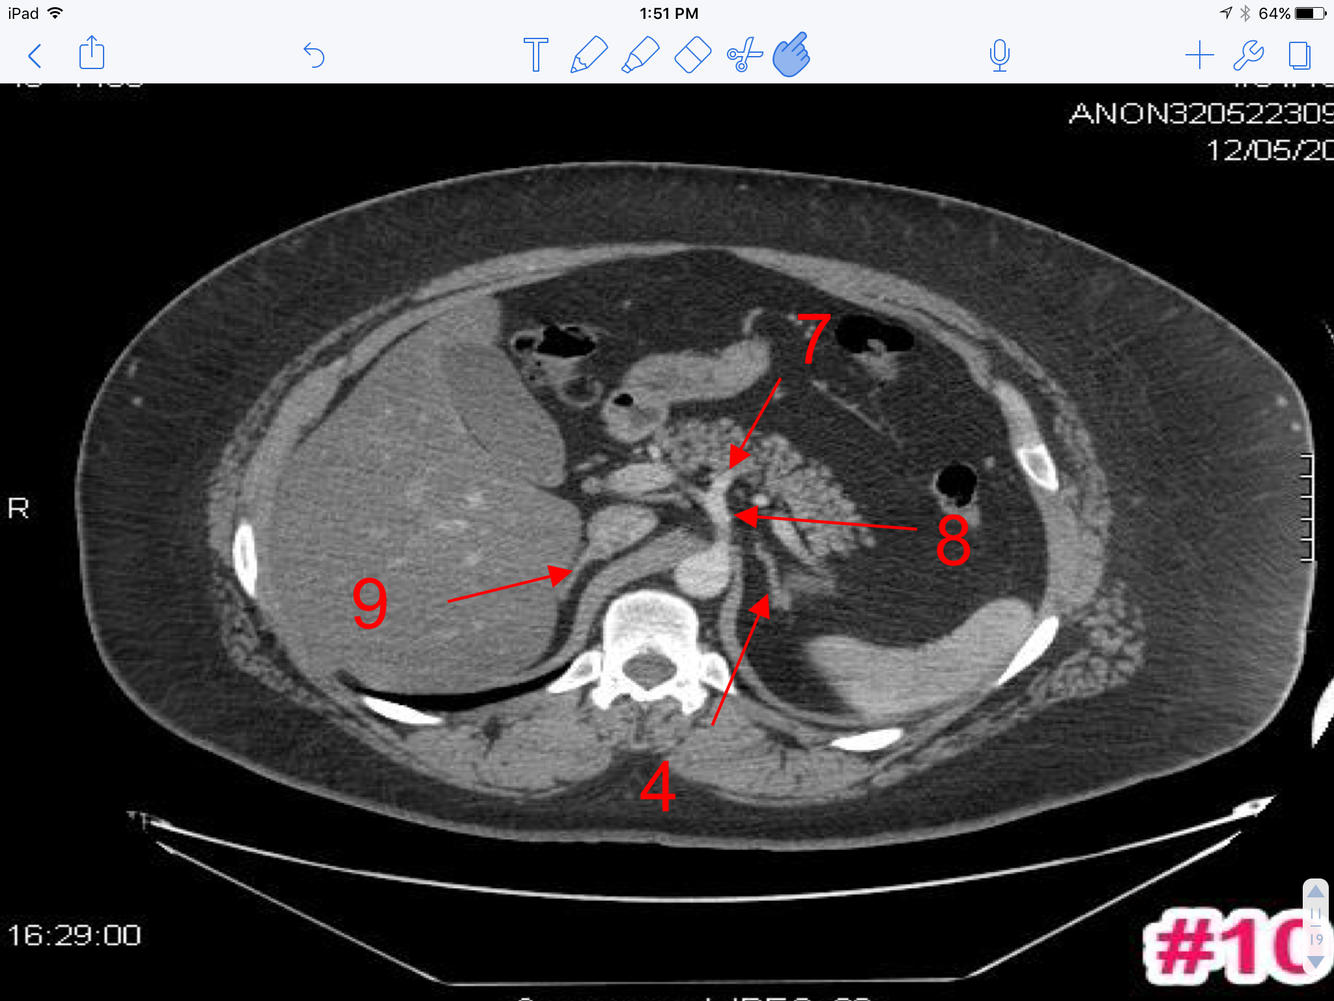

7

A

1. Body of gallbladder

2. Pyloric part of the stomach

3. Quadrate lobe of liver

4. Portal vein

5. Transverse colon

6. Descending colon